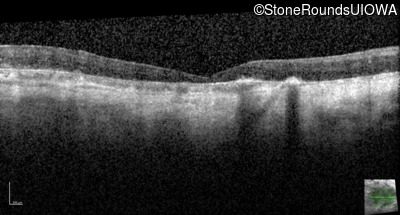

Age at visit: 42 years

Age at visit: 51 years